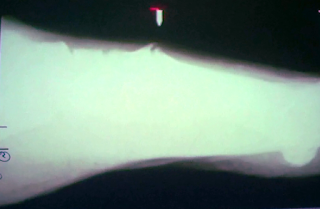

La imagen de arriba nos sugiere una posible fractura de calcáneo. Debemos

recordar que las fracturas de calcáneo se evalúan midiendo el ángulo de BHOLER.